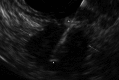

Significant advances in imaging technology have changed the management of pancreatic cancer. In computed tomography (CT), this has included development of multidetector row, rapid, thin-section imaging that has also facilitated the advent of advanced reconstructions, which in turn has offered new perspectives from which to evaluate this disease. In magnetic resonance imaging, advances including higher field strengths, thin-section volumetric acquisitions, diffusion weighted imaging, and liver specific contrast agents have also resulted in new tools for diagnosis and staging. Endoscopic ultrasound has resulted in the ability to provide high-resolution imaging rivaling intraoperative ultrasound, along with the ability to biopsy via real time imaging suspected pancreatic lesions. Positron emission tomography with CT, while still evolving in its role, provides whole body staging as well as the unique imaging characteristic of metabolic activity to aid disease management. This article will review these modalities in the diagnosis and staging of pancreatic cancer.